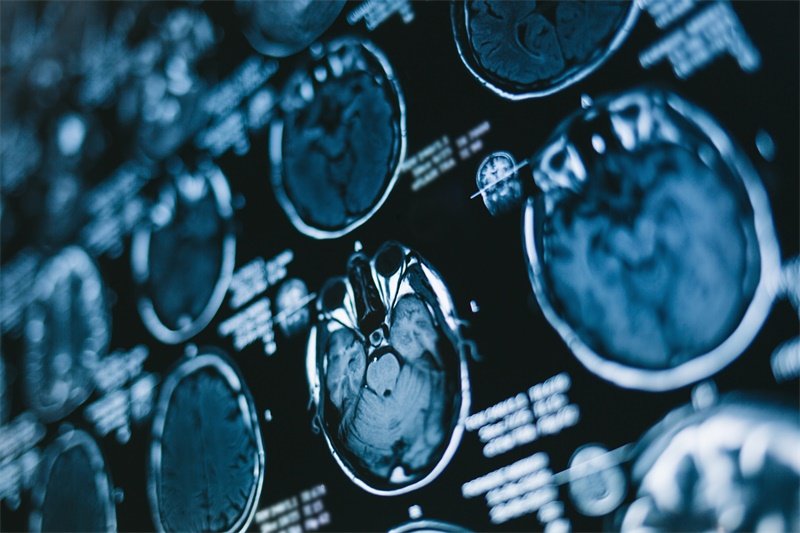

- 1. 影像学检查:如磁共振成像(MRI)或计算机断层扫描(CT)。